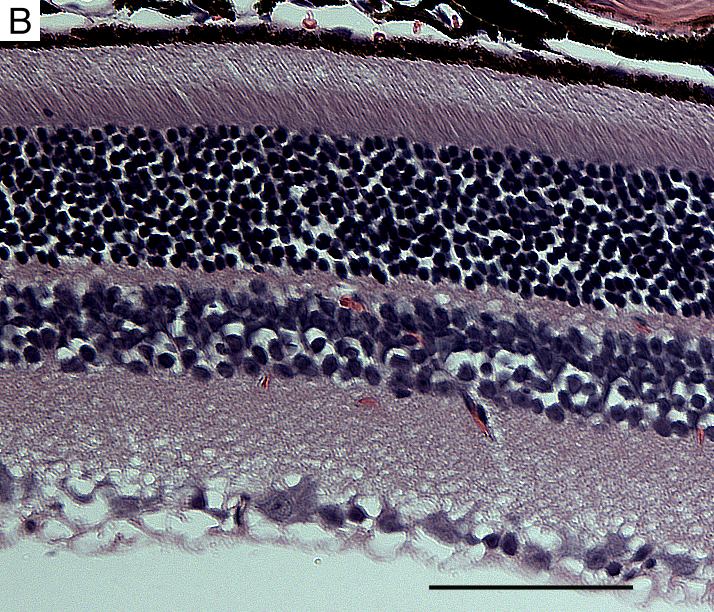

Figure 6. Retinal morphology in 6 month old HRGP-cre mice

Hematoxylin and eosin stained retinal section in 6 month old transgenic mouse (A) and wild type (WT) littermate (B). The scale bars represent 20 μm. No apparent abnormality was observed in 6 month old HRGP-cre mice.